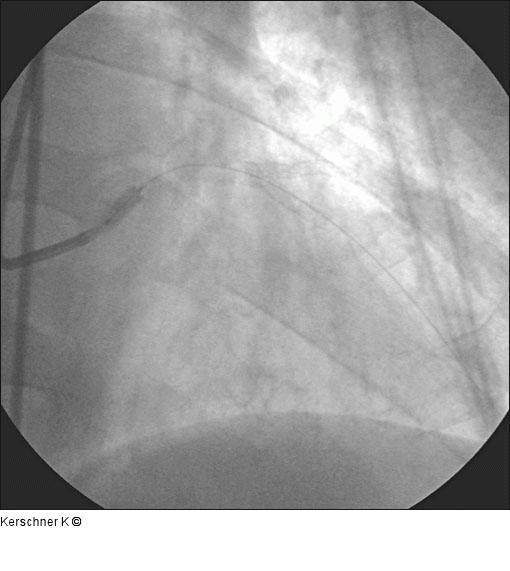

Abbildung 11: Primäre Stentimplantation - Ostiumhauptstamm Primäre Stentimplantation - Ostiumhauptstamm, Taxus Express 2 - 3,5/8 mm mit 16 atm. |

Primäre Stentimplantation - Ostiumhauptstamm, Taxus Express 2 - 3,5/8 mm mit 16 atm. |